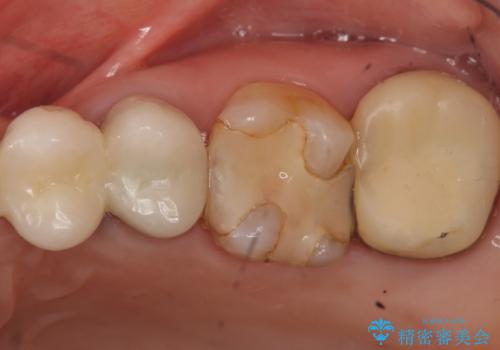

- 左上の奥歯がたまにしみるとのことで来院。視診・レントゲン画像より明らかに劣化した不適な修復物を確認しました。

同じ材料で同じように修復し直してもまた同じような予後になることが予想されるため、適合の良いセラミックインレーでの治療を提案させていただきました。

しかし向かい合わせになる歯の咬みこみが強く、インレーでは破折してしまうリスクが高いと予想し、より強固なクラウンで修復することになりました。